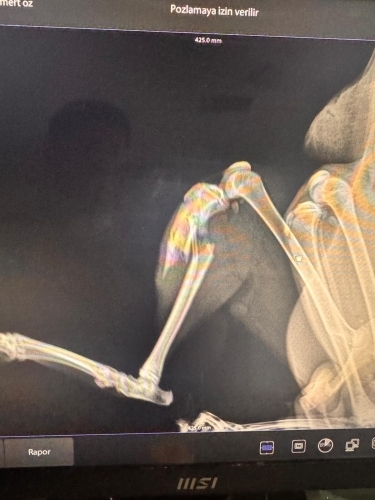

Adana, sarı beyaz, ben dün iç dış parazit yaptırdım geçmişini bilmiyorum, 11 aylık falan dedi veteriner, tuvaletini biliyor, sanırım bir cani bırakmış ve röntgen çektirdim ayağı kırılmış ve kaynamaya başlamış ameliyat olması lazım. Sahiplenmek istedim çokta sevdim 2 günde fakat öğrenciyim imkanım el vermiyor. Üzülerek sahiplendirmek zorundayım. Sokağa bırakamam zaten hırpalamışlar ve sokakta yapamaz. Her yere sordum ve sormaya devam ediyorum. Bir veteriner en azından destek verirse kendim de üstlenebilirim ama daha çok zaman kaybetmesini de istemiyorum. Düzgün bakmak şartıyla ve ameliyatını üstlenecek kişiye, ben çaresini bulamazsam sahiplendirmek zorundayım.